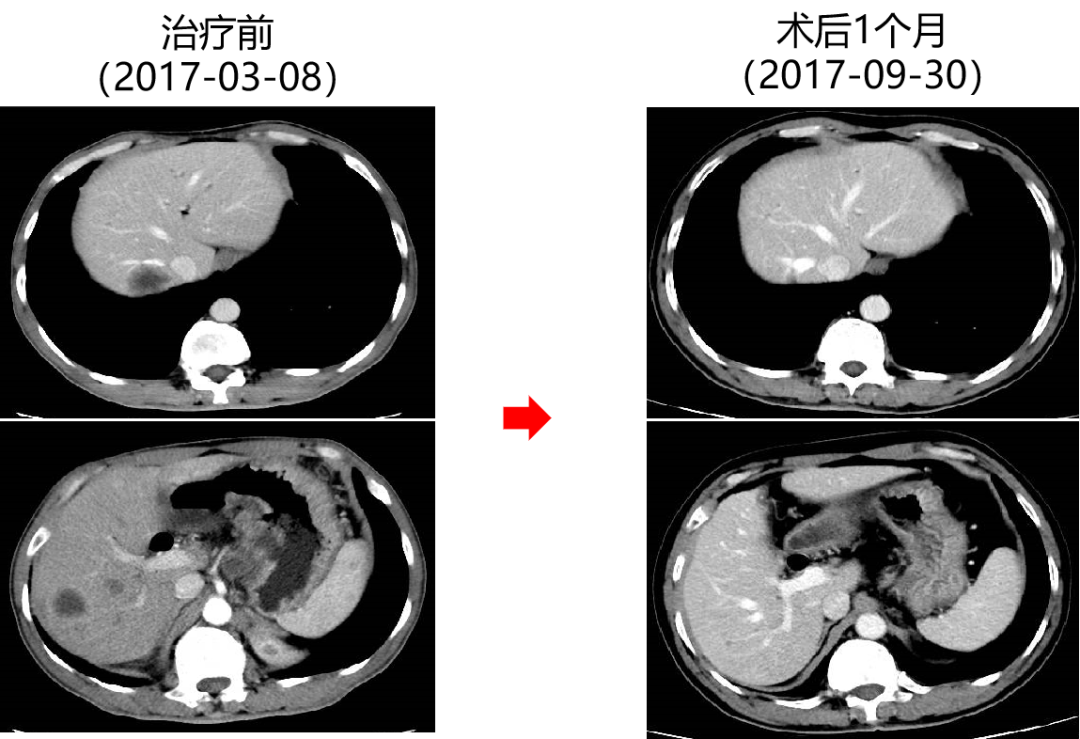

二 病例分享 专家简介 01 基本情况 患者:汪XX,男,63岁。身高 165cm;体重 65kg;体表面积 1.70m2;ECOG 1分。 主诉:反复解黏液血便3天。 对磁共振造影剂过敏,无食物、其他药物过敏史。既往史、个人史、婚育史、家族史均无特殊,无吸烟、饮酒史。 02 初诊病史 现病史:患者2017年3月初无明显诱因下解黏液血便,量中等,为鲜血,反复发作,无恶心、呕血、黑便、腹痛、腹泻、里急后重等不适。遂于2017年3月初就诊我院。 胸、腹、盆腔CT平扫+增强:乙状结肠肠壁明显增厚,肠腔狭窄,增强期强化明显;肝脏多发低密度病灶,增强期不规则强化,考虑乙状结肠癌伴肝脏多发转移。 03 治疗方案 【一线治疗】 2017-06-22 西妥昔单抗+FOLFIRI* Q2W×3 西妥昔单抗 900mg ivgtt D1; 5-氟尿嘧啶 0.6g iv D1,3.5g civ 48h; 亚叶酸钙 0.6g ivgtt D1; 伊立替康 280mg ivgtt D1。 第1疗程结束后黏液血便较前消失,过程顺利,耐受良好,无皮疹、腹泻等不良反应,治疗10疗程,疾病进展。 疗效评估-影像学(部分缓解,PR)。 2017-07-15 乙状结肠癌切除术* 手术记录:肿瘤位于乙状结肠,大小约4cm×3cm,未突破浆膜层,病灶周围可及数个稍肿大淋巴结,未及盆底种植结节。 手术过程顺利,术后恢复良好。 术后病理:(乙状结肠)中分化腺癌,浸润肠壁浆膜下层,两切缘阴性,未见脉管癌栓及神经束侵犯,LN 2/18(+) 2017-08-20 肝转移瘤切除术* 手术记录:肝脏肿瘤位于肝右叶,大小分别约2cm×1.5cm,1cm×1.2cm,其余肝表面未见异常结节,腹腔无腹水、无粘连。 手术过程顺利,术后恢复良好。 术后病理:(肝右叶病灶)中分化腺癌,结合临床病史,符合乙状结肠癌肝转移,肝组织切缘未见癌。 疗效评估-影像学(NED)。 2017-11-06 西妥昔单抗+FOLFIRI* Q2W×3 西妥昔单抗 900mg ivgtt D1; 5-氟尿嘧啶 0.6g iv D1,3.5g civ 48h; 亚叶酸钙 0.6g ivgtt D1; 伊立替康 280mg ivgtt D1; 过程顺利,无皮疹、腹泻等不良反应。每疗程后均予PEG-CSF预防性升白,耐受良好。 疗效评估-影像学(病情进展,PD1)。 胸、腹、盆腔CT平扫+增强:肝左外叶低密度灶,增强期不规则强化,结合病史,考虑结肠癌肝转移,余未见明显异常。 【二线治疗】 2018-03-06 肝左外叶肿瘤切除术* 术中探查见:肿瘤位于肝左外叶,质硬,边界不清,余肝脏表面未见异常结节灶,腹盆腔无腹水。 手术过程顺利,术后恢复良好。 术后病理示:(肝左叶)中分化腺癌,结合临床病史,符合结肠腺癌肝转移。 2018-04至2018-07 卡培他滨+奥沙利铂* Q3W×5 卡培他滨 1.5g BID D1-14; 奥沙利铂 200mg ivgtt D1。 过程顺利、耐受良好,无腹泻、神经毒性等不良反应。 疗效评估-影像学(病情进展,PD2)。 胸、腹、盆腔CT平扫+增强:肝尾状叶结节状异常密度灶,增强期不规则强化,结合病史,考虑结肠癌肝转移,余未见明显异常。 2018-07至2020-04 贝伐珠单抗+卡培他滨* Q3W×21 贝伐珠单抗 500mg ivgtt D1; 卡培他滨 1.5g BID D1-14。 过程顺利、耐受良好,期间曾出现II度腹泻,对症治疗后可恢复正常。无血压升高、出血、蛋白尿、手足皮肤反应。 疗效评估-影像学(最佳疗效,PR)。 疗效评估-影像学(病情进展,PD3)。 腹腔镜肝尾状叶切除术+腹腔粘连松解术* 术中探查见:肿瘤位于肝尾状叶,质硬,边界不清,余肝脏表面未见异常结节灶,腹盆腔无腹水。 手术过程顺利,术后恢复良好。 术后病理示:(肝尾状叶)中分化腺癌,结合临床病史,符合结肠腺癌肝转移。 2020-06至2021-09 贝伐珠单抗+卡培他滨* Q3W×16 贝伐珠单抗 500mg ivgtt D1; 卡培他滨 1.5g BID D1-14。 过程顺利、耐受良好,期间曾出现II度腹泻,对症治疗后可恢复正常。无血压升高、出血、蛋白尿、手足皮肤反应。 疗效评估-影像学(NED)。 疗效评估-影像学(NED)。 【三线治疗】 2021-12-16 西妥昔单抗+TAS-102* Q3-4W×2 西妥昔单抗 900mg ivgtt D1; TAS-102 60mg BID D1-5,8-12。 过程顺利、耐受稍差,期间出现II度骨髓抑制(三系减少),对症治疗后可恢复正常。无皮疹、输液反应等。 疗效评估-影像学(部分缓解,PR)。 04 治疗小结